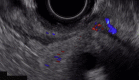

Every trick in the book: EUS angiotherapy for management of refractory bleeding secondary to a complicated duodenal ulcer in a patient with Roux-en-Y gastric bypass